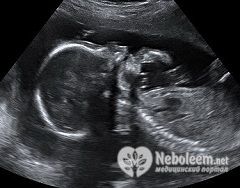

Плановое УЗИ на 20 неделе беременности является необходимым минимумом исследований для всех женщин на этом сроке. Всего за нормально протекающую беременность женщине рекомендуют пройти не менее 3 ультразвуковых исследований в 10, 20 и 30 недель.

По результатам УЗИ оценивают размер плода на 20 неделе беременности и его соответствие сроку. УЗИ в 20 недель беременности чаще всего позволяет определить половую принадлежность будущего малыша.